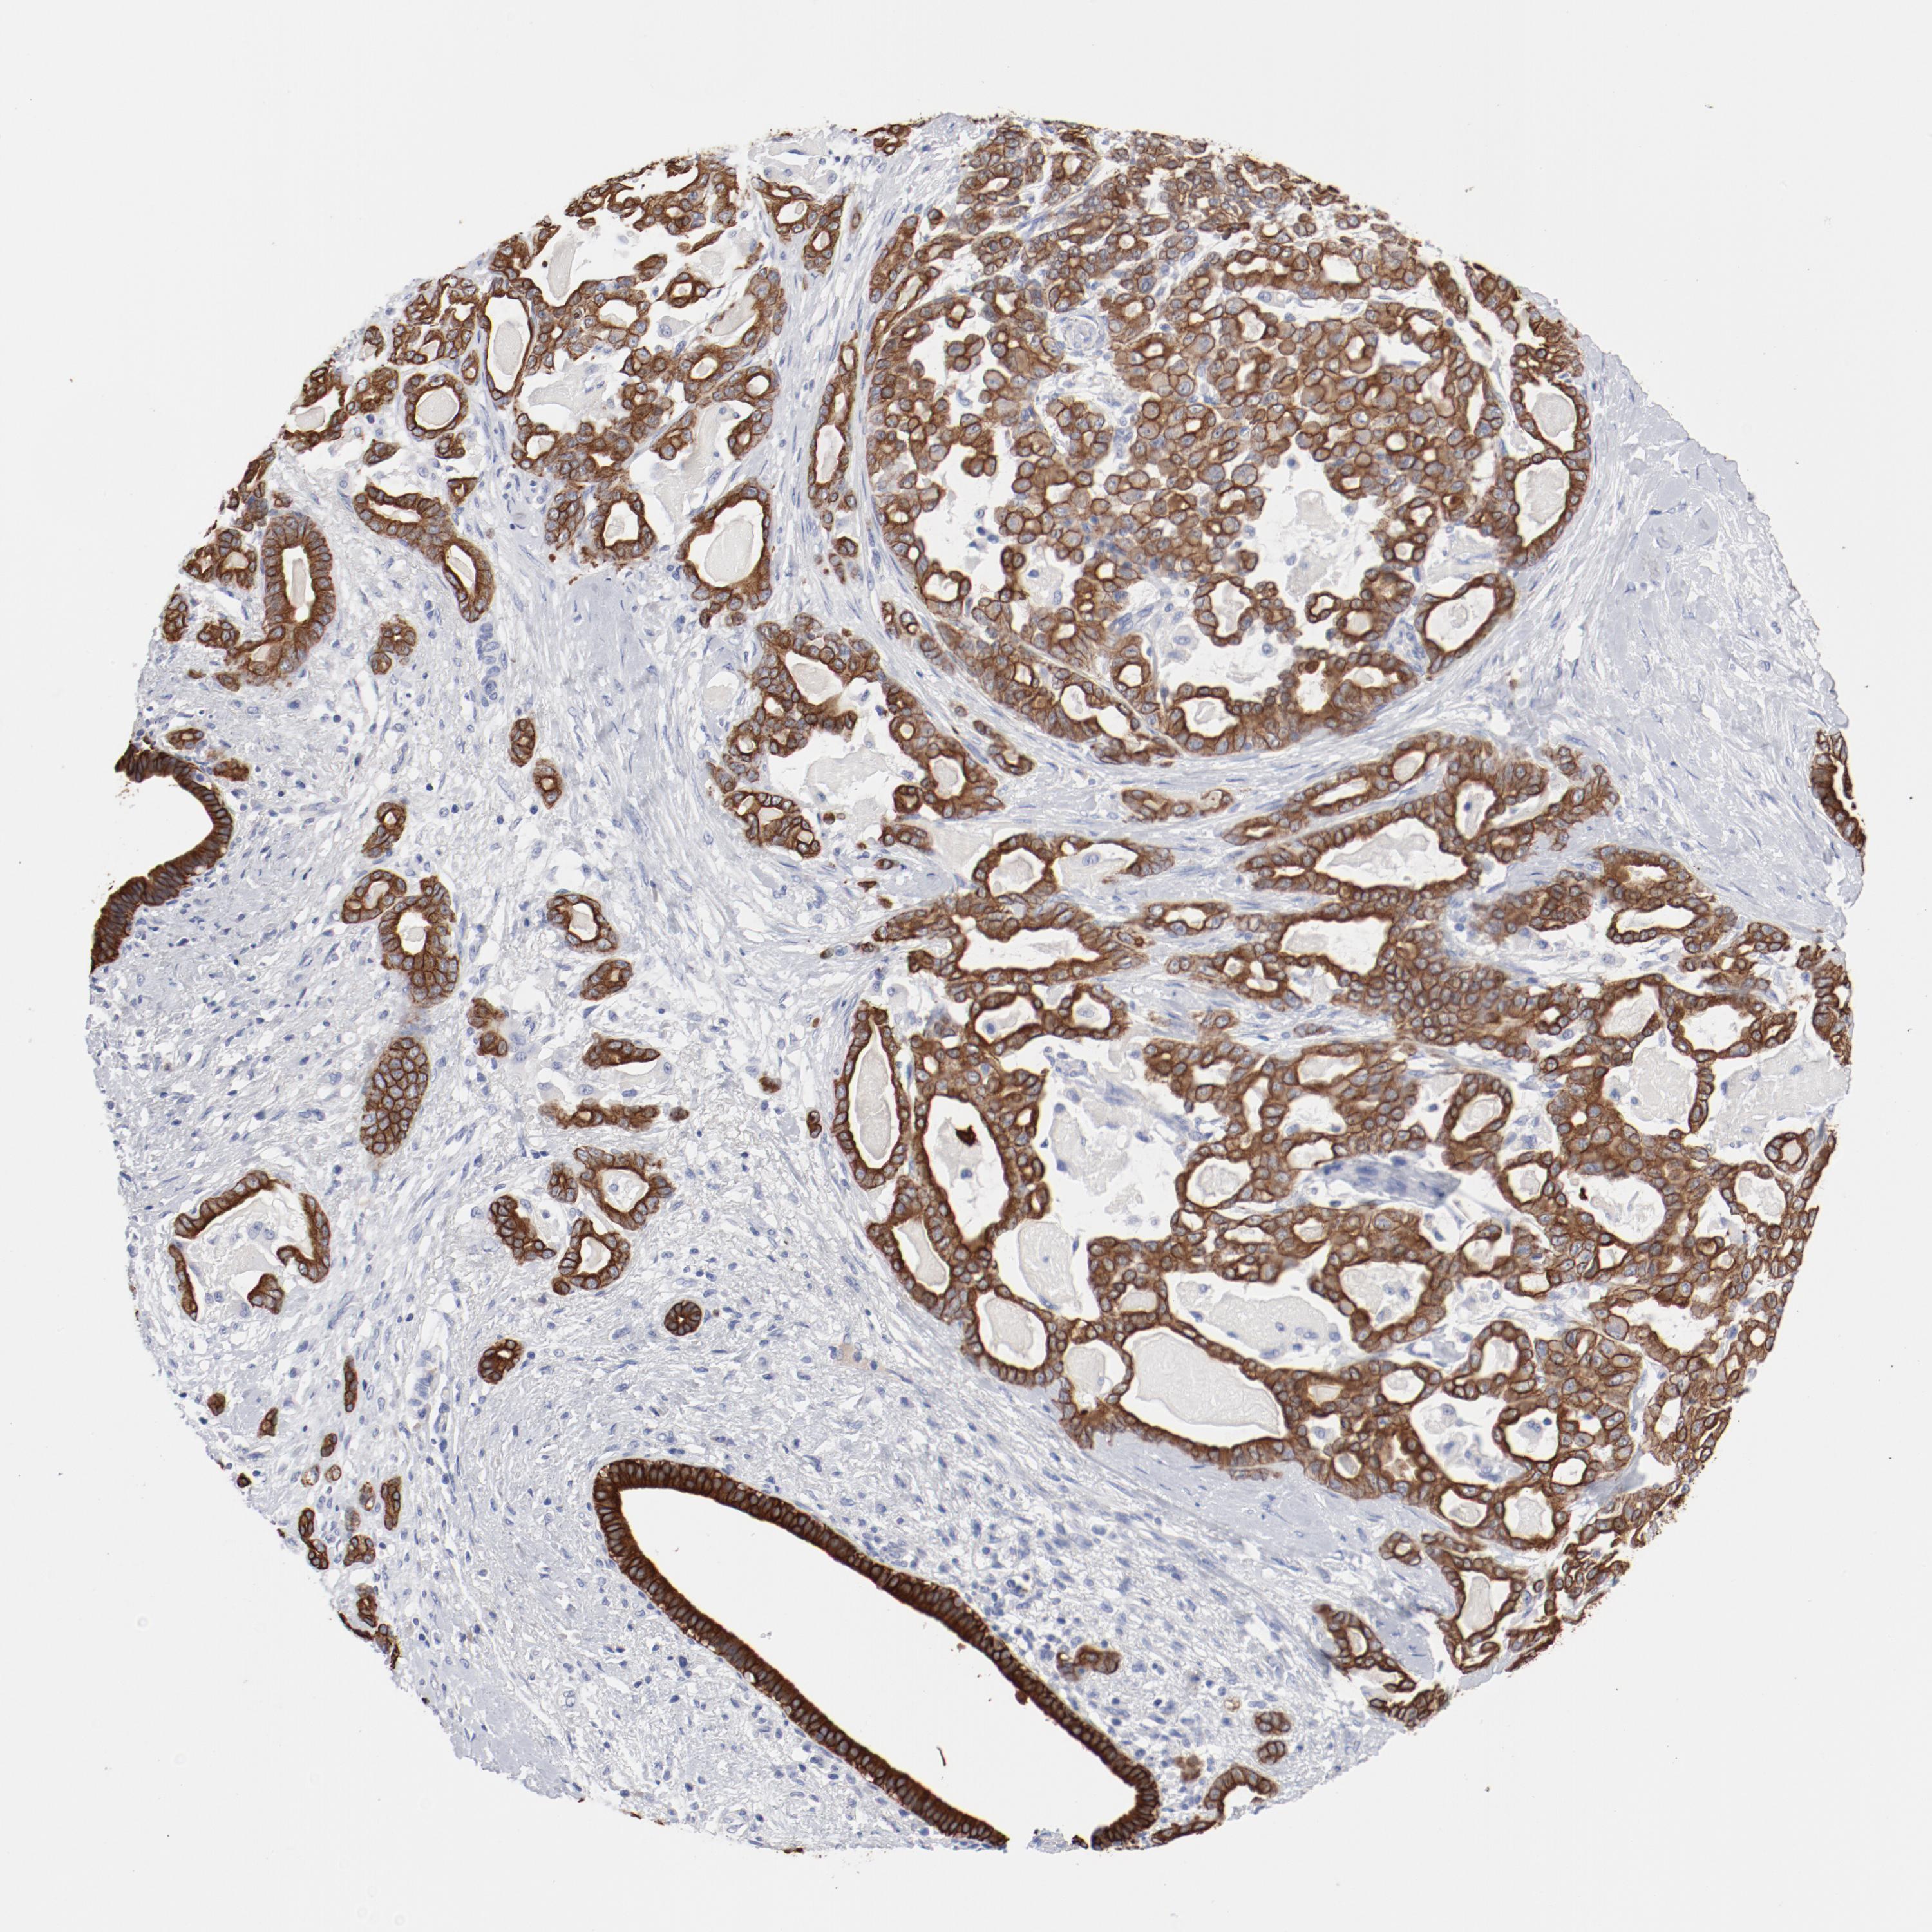

PANCREATIC CANCER - Protein expressioni

A mouse-over function shows sample information and annotation data. Click on an image to view it in a full screen mode. Samples can be filtered based on level of antibody staining by selecting one or several of the following categories: high, medium, low and not detected. The assay and annotation is described here.

Note that samples used for immunohistochemistry by the Human Protein Atlas do not correspond to samples in the TCGA dataset.

Antibody stainingi

Antibody staining in the annotated cell types in the current human tissue is reported as not detected, low, medium, or high, based on conventional immunohistochemistry profiling in selected tissues. This score is based on the combination of the staining intensity and fraction of stained cells.

Each image is clickable and will lead to virtual microscopy that enables deeper exploration of all samples and also displays staining intensity scores, fraction scores and subcellular localization as well as patient and tissue information for each sample.

Antibody HPA004109

Staining

High

Medium

Low

Not detected

Intensity

Strong

Moderate

Weak

Negative

Quantity

>75%

75%-25%

<25%

None

Location

Nuclear

Cytoplasmic/membranous

Cytoplasmic/membranous,nuclear

Adenocarcinoma, NOS

Adenocarcinoma, metastatic, NOS